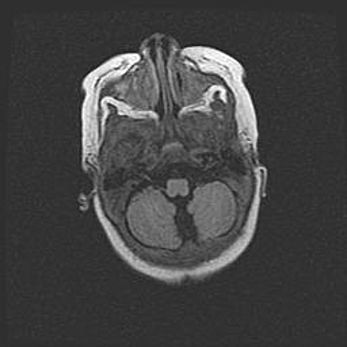

Церебральная ишемия II.

Возраст: 7 дней

Вес: 3350 г

Пол: женский

Окружность головы: 35 см

Срок гестации: 39 недель

Ишемия головного мозга – это состояние, которое развивается в ответ на кислородное голодание вследствие недостаточного мозгового кровообращения. У новорожденных она является следствием дефицита кислорода, что ведет к метаболическим расстройствам различной степени тяжести в тканях головного мозга, в том числе к развитию коагуляционных некрозов и гибели нейронов.